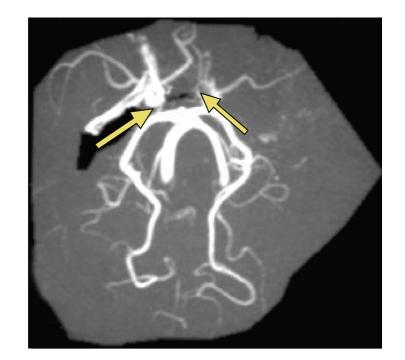

The challenge in acute stroke is still to reperfuse as early as possible the ischemic territory. Since fibrinolytic therapies have a limited window with potential risk of bleeding, having a nonpharmacologic mean to recruit vessels in area surrounding necrosis might be useful. We propose here to use antigravity suit inflated at "venous" pressure levels to shift blood towards thoracic and brain territories. We report two cases of spectacular clinical recovery after acute carotid occlusion.

急性中风的挑战仍然是尽早使缺血区域再灌注。由于纤维蛋白溶解疗法的时间窗有限且有潜在出血风险,采用一种非药物手段来促使坏死区域周围的血管恢复供血可能会有所帮助。我们在此提议使用在“静脉”压力水平充气的抗重力服,将血液转移至胸部和脑部区域。我们报告了两例急性颈动脉闭塞后临床症状显著恢复的病例。